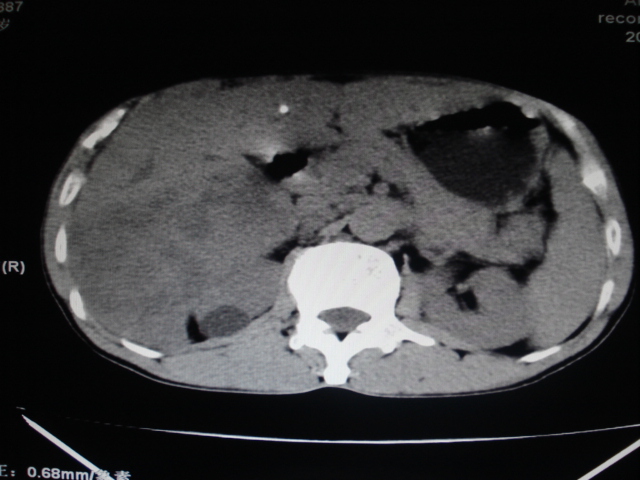

男性,62岁。肝右叶占位,平扫及增强如下,延迟期为15分钟扫描。